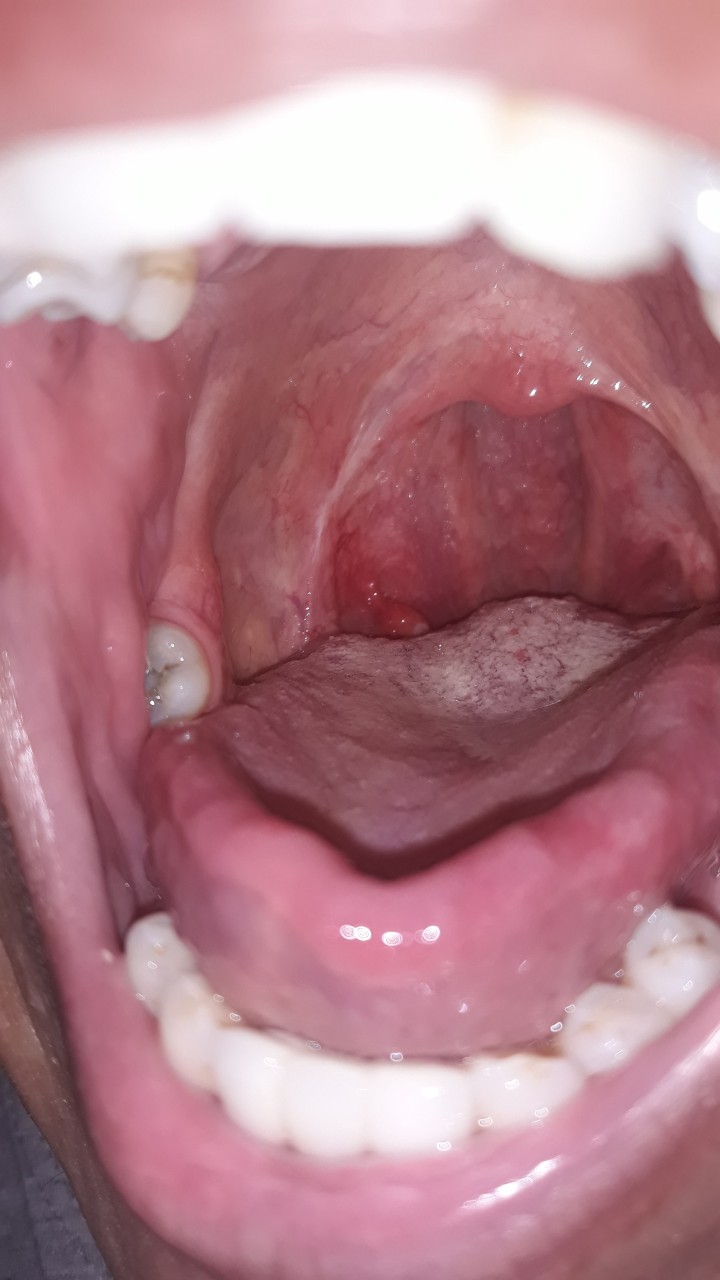

После применения люголя воспаление уменьшилось . И теперь периодически этот нарост воспаляется, увеличиваясь в размерах, в это время из-за него даже больно принимать пищу . В принципе после удаления миндалин с правой стороны ( на месте миндалины) появились неприятные ощущения, при движениях языком там тянет и что-то мешает .

Больше чем полтора года назад мне провели операцию по удалению нёбных миндалин . Меня в принципе ничего не беспокоило . . . Но вот буквально пару дней назад я обнаружила нарост на месте удалённой гланды, напоминающий маленький сосочек . . . Он создаёт небольшие неудобства . . .